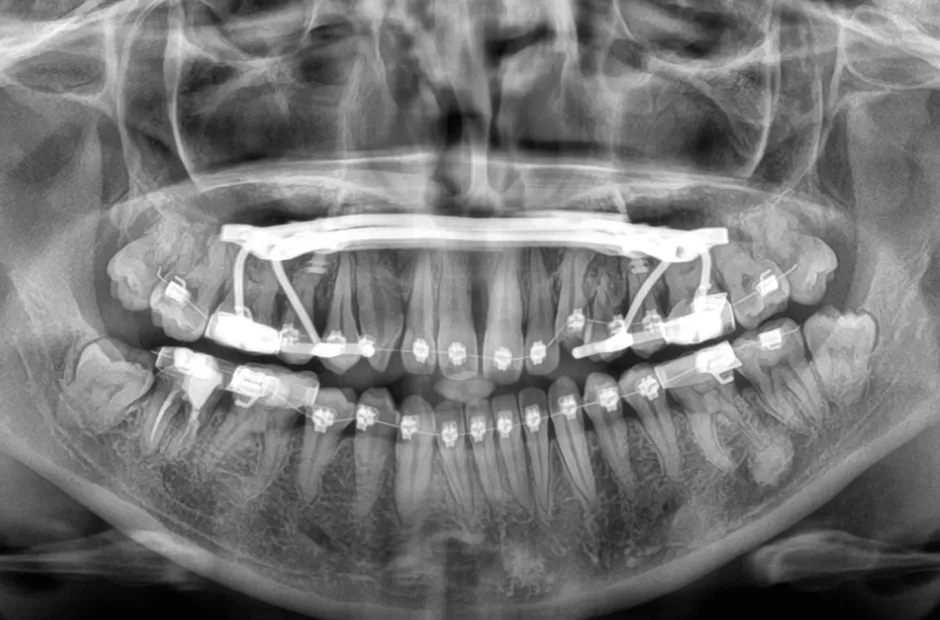

叢生

| 診断名・主訴 | 叢生 |

|---|---|

| 年齢・性別 | 43歳・女性 |

| 治療期間・回数 | 2年7か月 27回 |

| 治療に用いた主な装置 | 舌側矯正 |

| 抜歯部位 | 両顎4,4 |

| 治療費 | 100万円(税抜) |

| リスク・副作用 | 装置による違和感・疼痛・歯肉退縮・歯根吸収・虫歯のリスクなど |

治療前

治療中

治療後